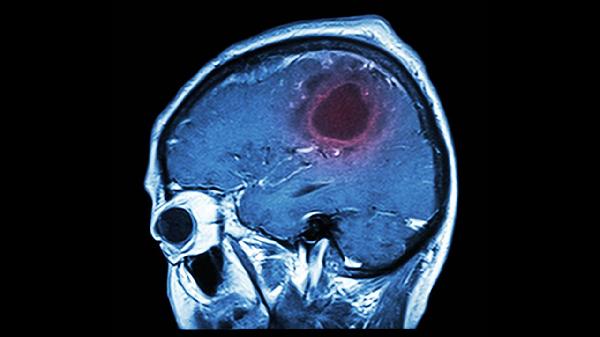

脑实质型是囊尾蚴寄生在大脑皮层或深部灰质核团引起的类型。患者可能出现癫痫发作、头痛、肢体无力等症状。病灶多呈多发小圆形低密度影,周围伴有水肿带。该型需与脑肿瘤、结核瘤等疾病鉴别诊断。治疗可采用阿苯达唑片联合泼尼松片控制炎症反应,严重时需手术切除病灶。